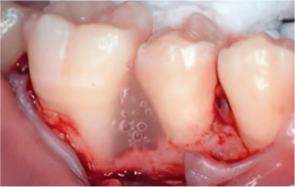

Emdogain application

-

STEP 05

Cleansing